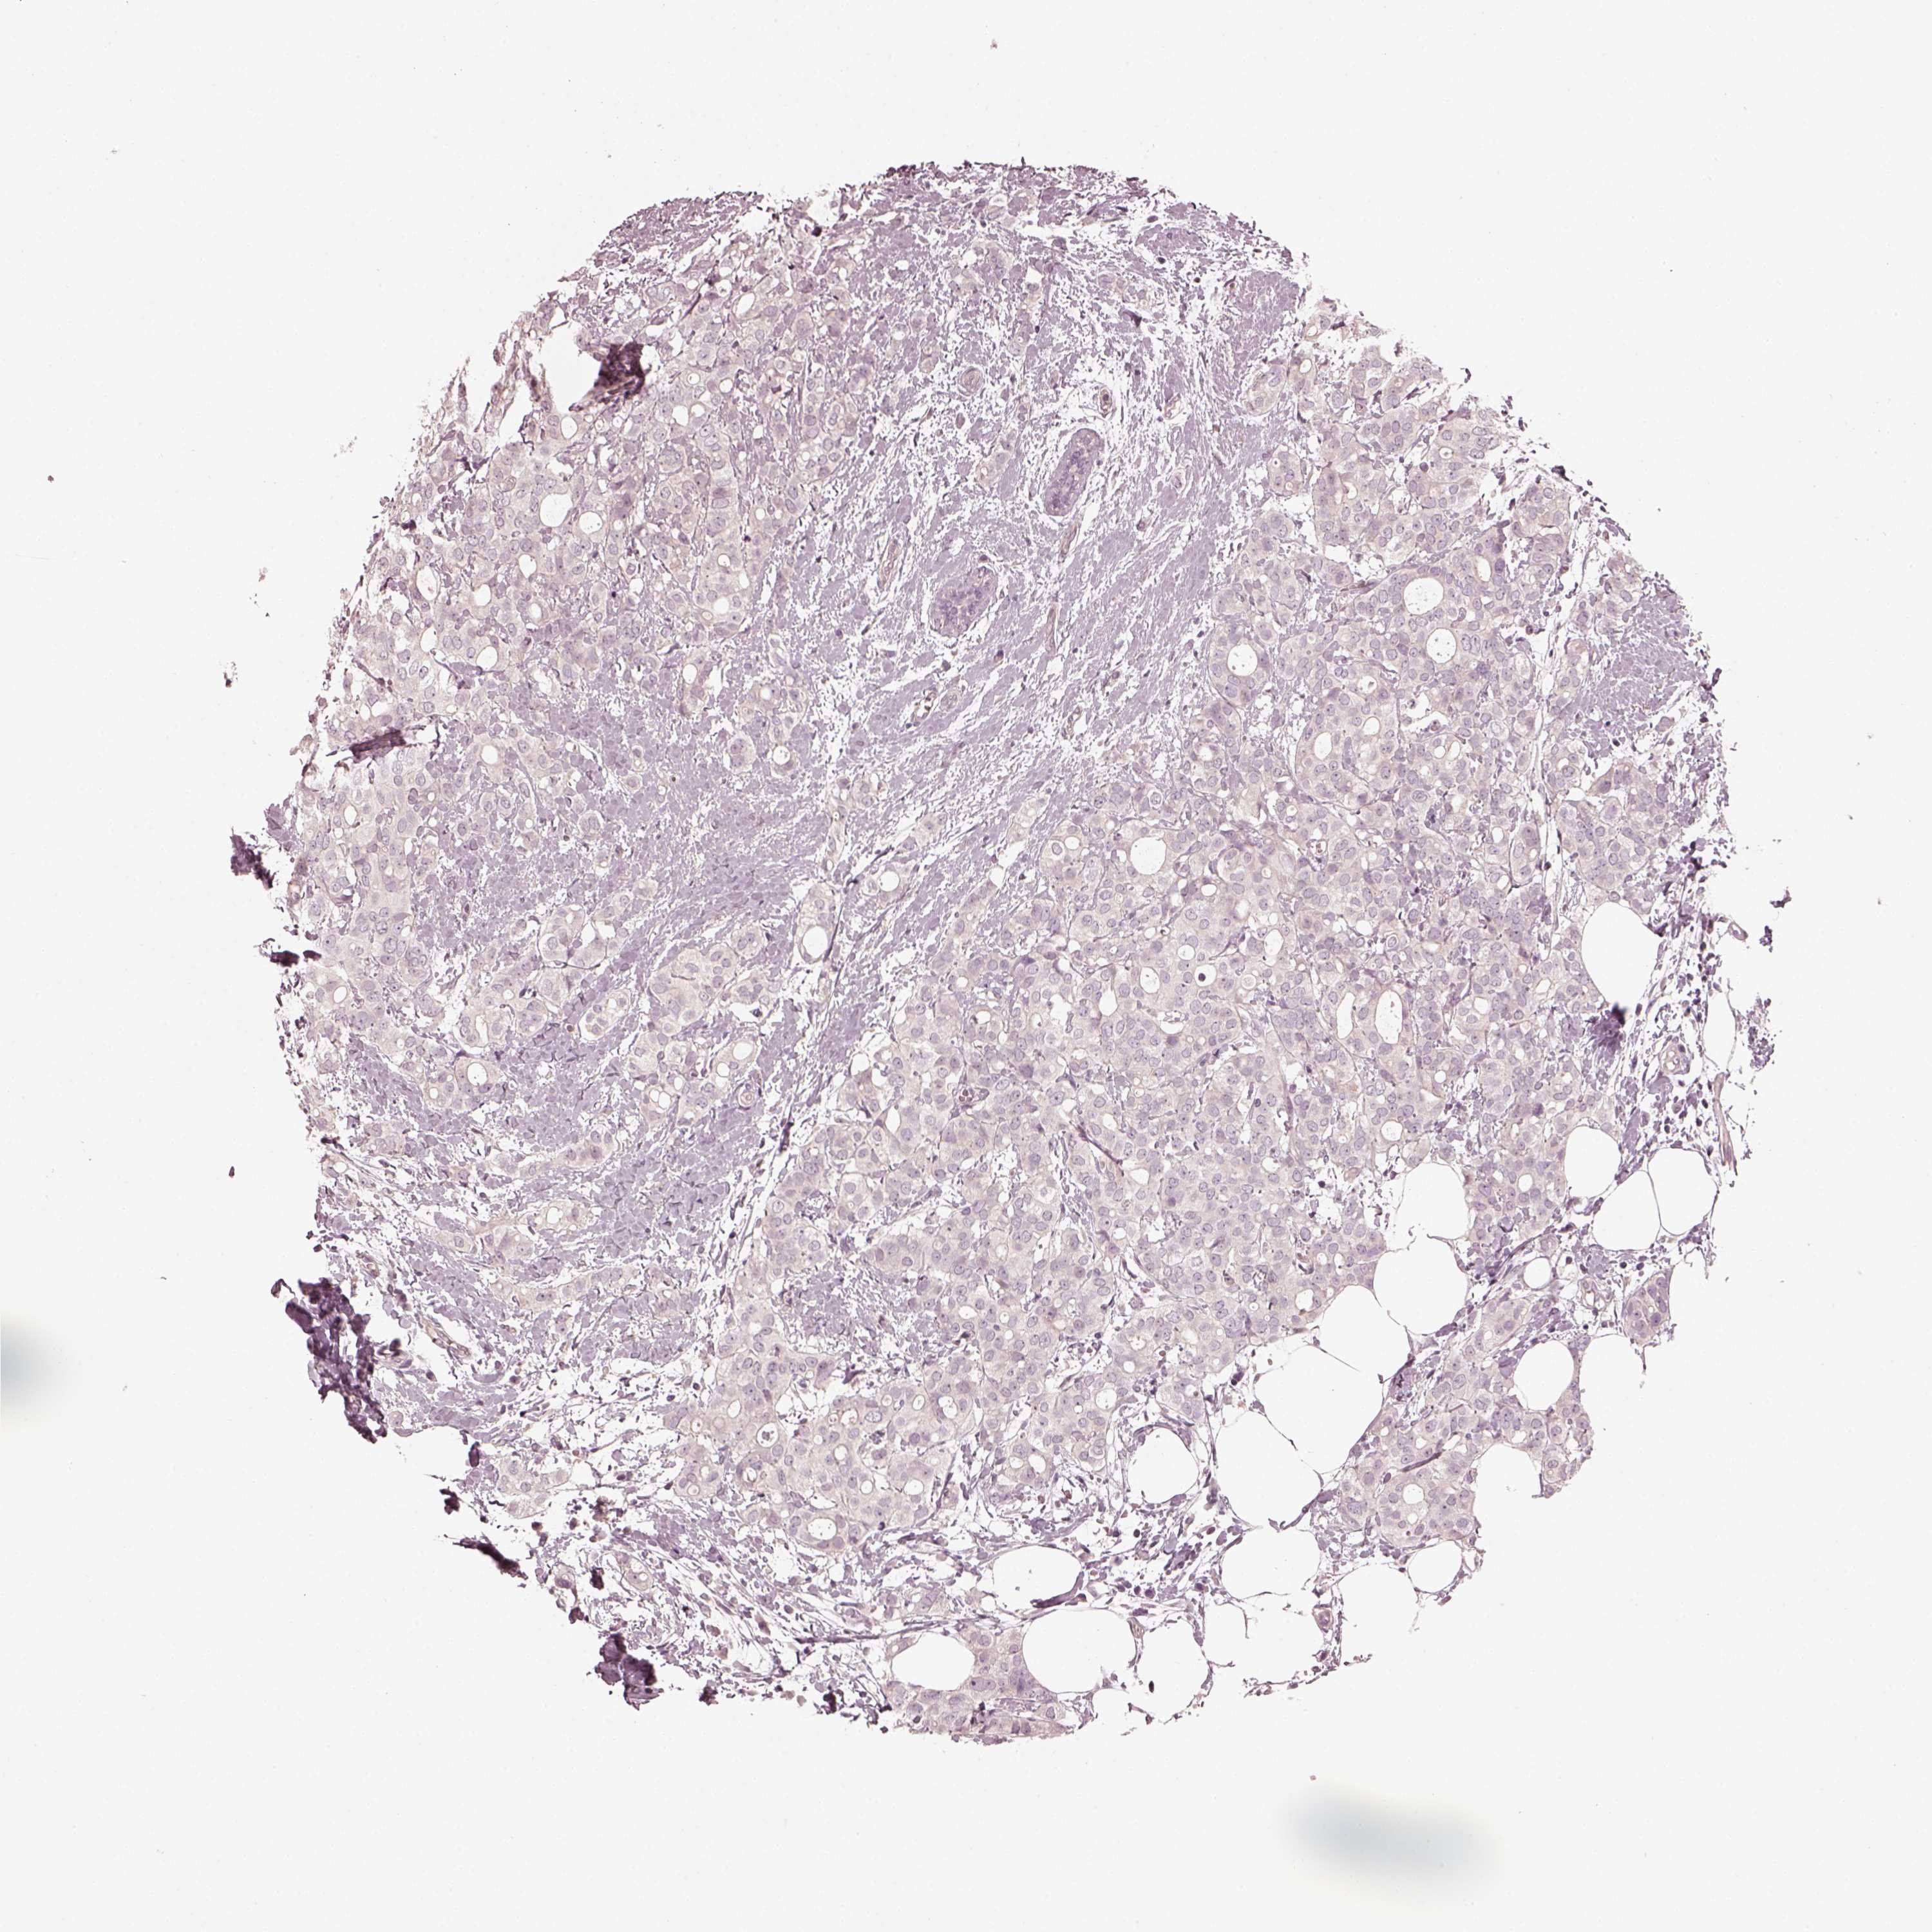

BRCA TCGA BRCA VALIDATION PROTEIN EXPRESSION